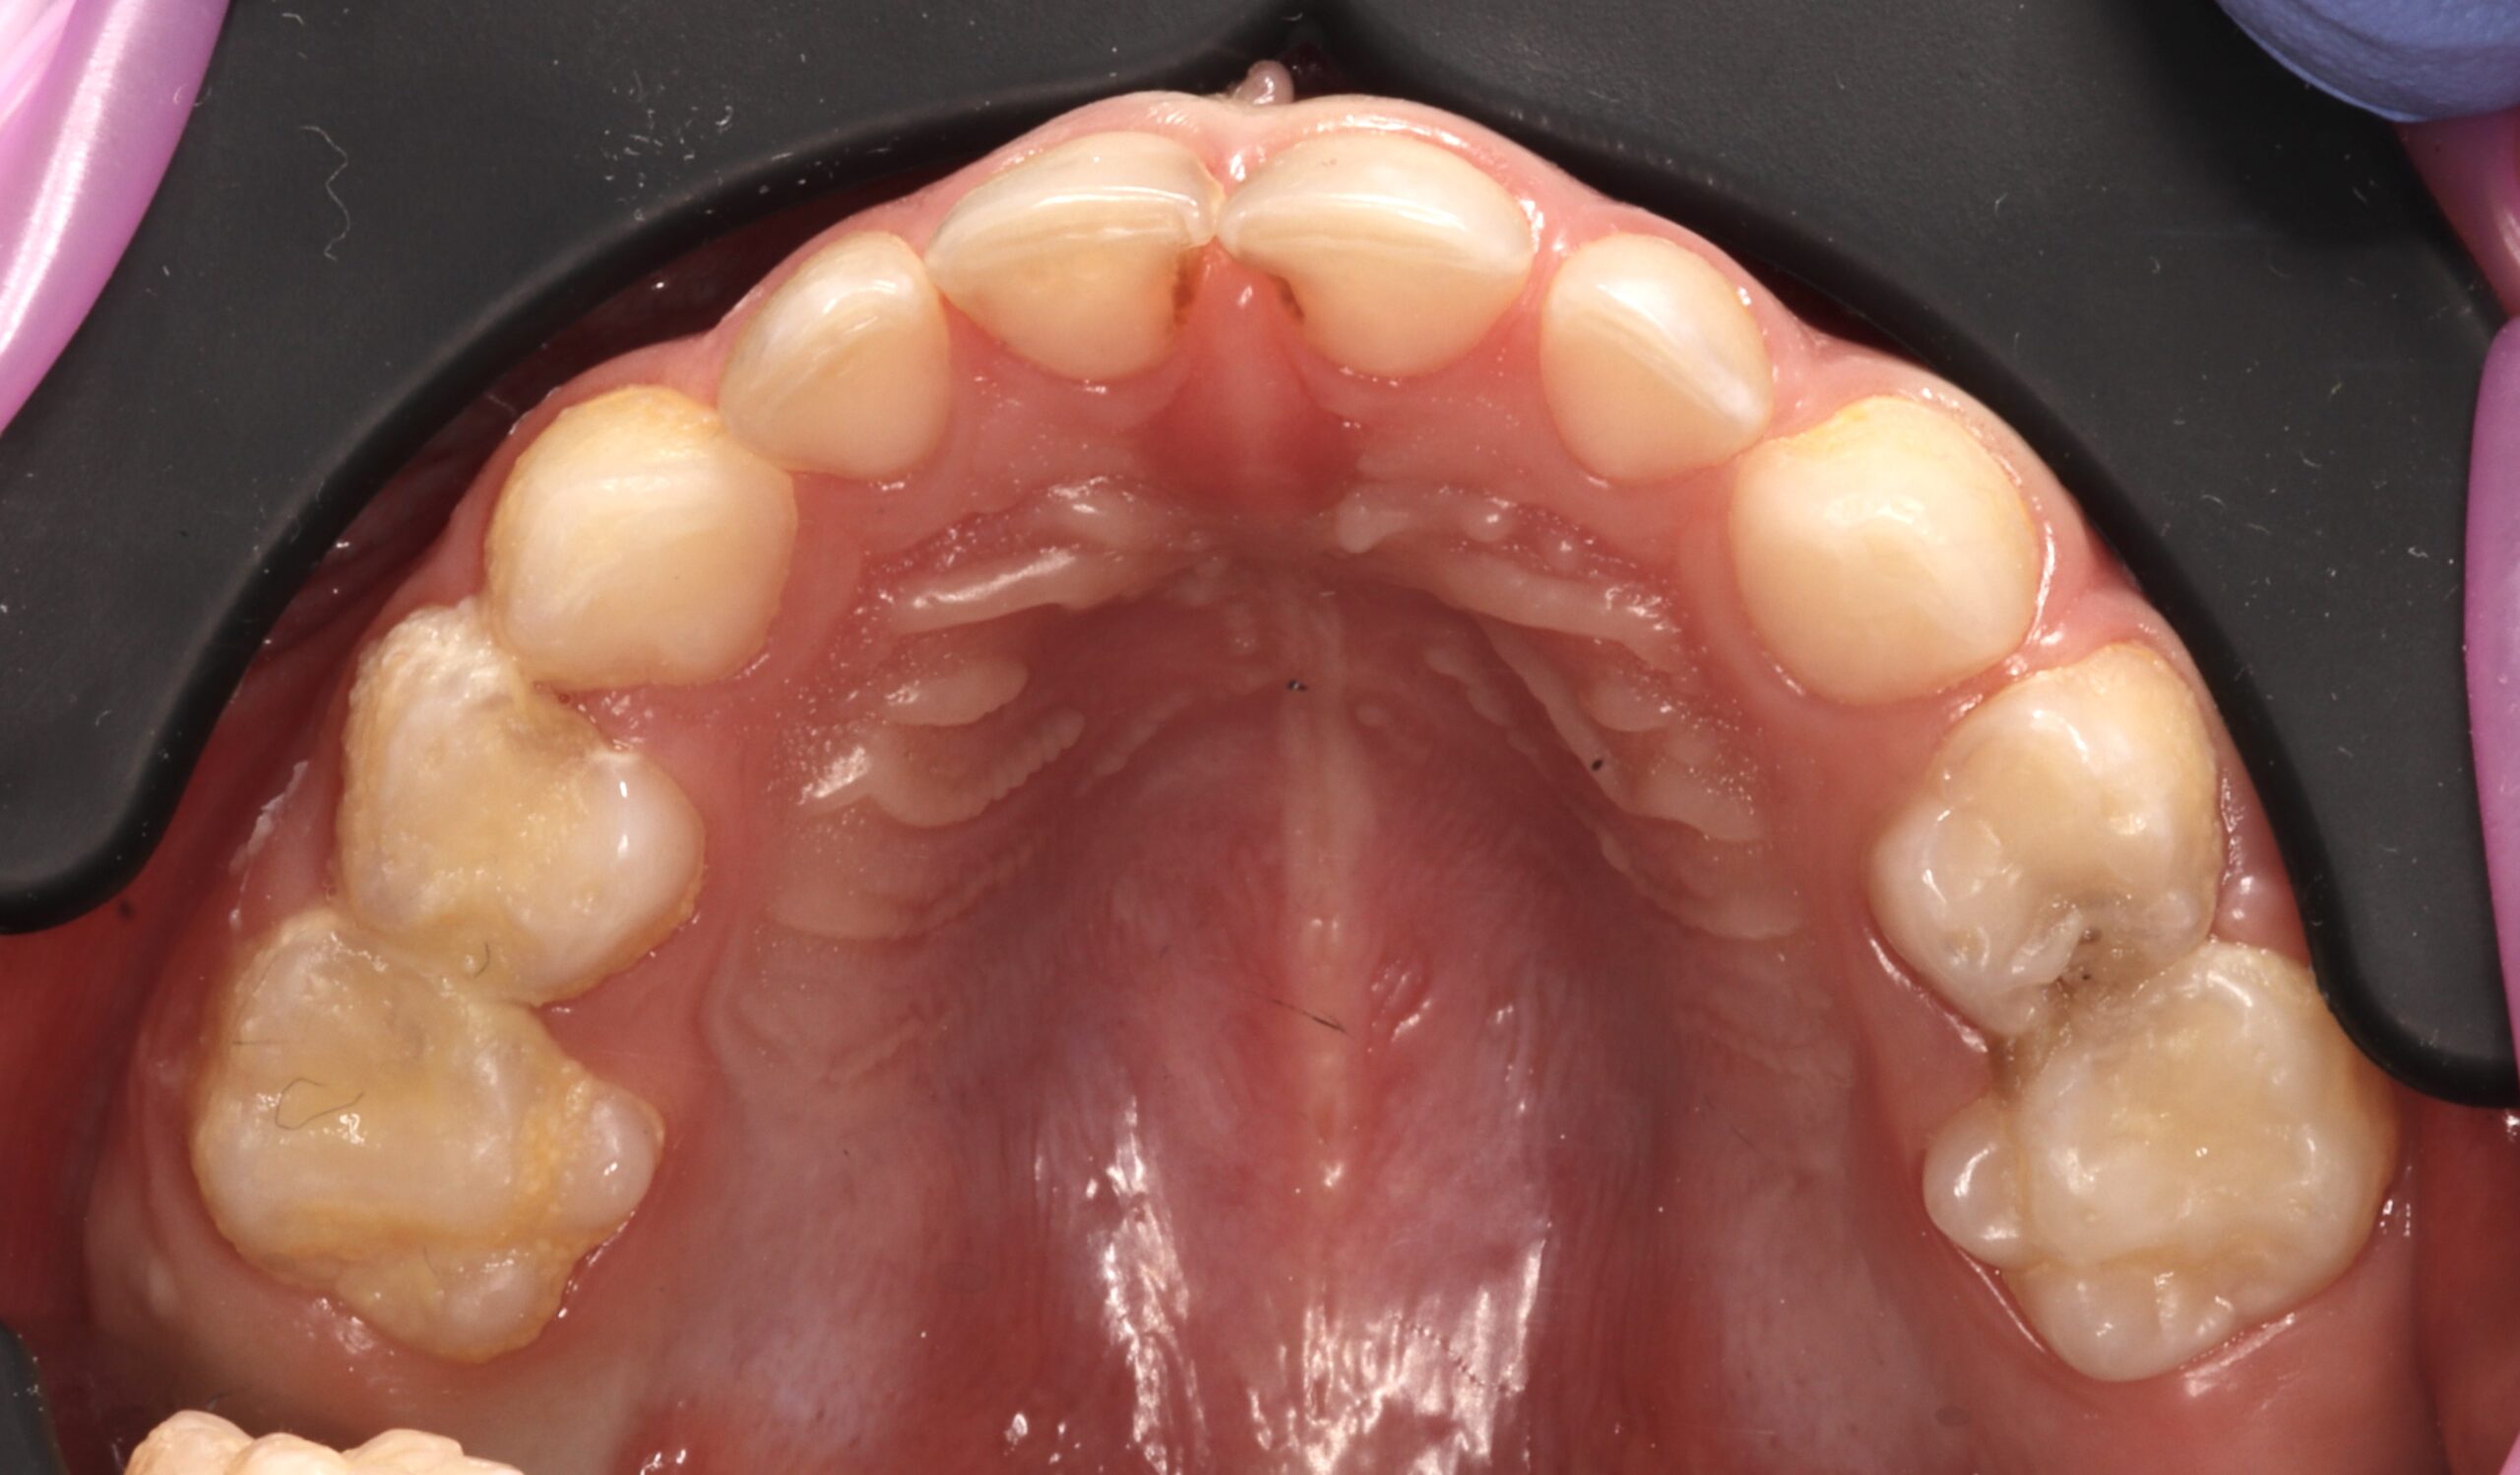

Тельтаева Рамина Талгатовна

Работает с любовью к детям и уважением к их особенностям.

Начала карьеру в Kids Smile ассистентом, получила опыт под руководством ведущих специалистов

Прошла обучение у врачей из Кореи, Японии, Беларуси и России